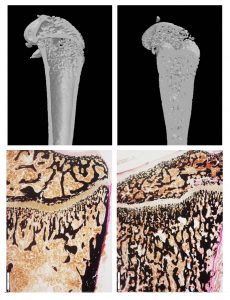

Deutsche, Israelis und Palästinenser wollen gemeinsam die Marmorknochenkrankheit besiegen26. April 2019 Jan Tuckermann, Leiter des Instituts für Molekulare Endokrinologie der Tiere, forscht mit israelischen und palästinensischen Wissenschaftlern zur Erbkrankheit Osteopetrose. (Foto: Eberhardt/Uni Ulm) In einem trilateralen Projekt wollen deutsche, israelische und palästinensische Wissenschaftler die Marmorknochenkrankheit (Osteopetrose) erforschen. Diese eigentlich seltene Erbkrankheit kommt in palästinensischen Großfamilien auffällig häufig vor. Im Zuge des Forschungsprojekts ist es den Wissenschaftlern um Prof. Jan Tuckermann von der Universität Ulm nicht nur gelungen, die Stammbäume betroffener Familien zu rekonstruieren. Sie haben zudem wichtige molekulare Grundlagen der Osteopetrose aufgedeckt. Der politisch angespannten Lage zum Trotz arbeiten die Forschenden hervorragend zusammen: Kinder mit der lebensbedrohlichen Krankheit werden in israelischen Krankenhäusern behandelt. Die Marmorknochenkrankheit ist eine Erberkrankung mit schweren Folgen: Durch eine Störung beim Knochenabbau und einer dementsprechend erhöhten Knochendichte ist das Wachstum betroffener Kinder gehemmt. Darüber hinaus kann eine Schädigung der Hirn- und Sehnerven zu geistigen Defiziten und zur Erblindung führen. Eigentlich gilt die Osteopetrose als seltene Erkrankung, doch bei palästinensischen Großfamilien tritt sie auffällig häufig auf. Um die Ursachen dieser Erbkrankheit zu ergründen und neue Therapieansätze zu entwickeln, bündeln deutsche, israelische und palästinensische Forschende ihre Kompetenzen. Ihre Forschungsergebnisse kommen nicht nur von Osteopetrose betroffenen Familien in den Palästinensergebieten zugute, sie könnten auch zu einem tieferen Verständnis der Volkskrankheit Osteoporose führen. Nun hat die Deutsche Forschungsgemeinschaft (DFG) eine Weiterförderung des trilateralen Projekts bis 2022 mit rund 570 000 Euro beschlossen. Bei der Osteopetrose ist, wie bei der Osteoporose auch, die Balance zwiscgeb Knochenauf- und -abbau gestört. Wird die Osteopetrose frühzeitig erkannt, können betroffene Kinder durch eine Knochenmarktransplantation geheilt werden – doch diese Behandlung ist riskant. Jetzt wurde bei Osteopetrose-Patienten aus den besonders betroffenen Palästinensergebieten eine Erbgutveränderung entdeckt, die der Schlüssel zu alternativen Therapieansätzen sein könnte. Dieser Erbgutveränderung geht eine internationale Forschergruppe um den Ulmer Biologen Prof. Jan Tuckermann auf den Grund – insbesondere mithilfe von genetischen und zellbiologischen Methoden. In ihrem trilateralen Forschungsprojekt arbeiten die Naturwissenschaftler der federführenden Universität Ulm eng mit dem renommierten israelischen Weizmann-Institut sowie mit der Bethlehem University (Palästinensische Autonomiegebiete) zusammen. Als erster Erfolg ist es den Forschenden gelungen, die Stammbäume von Trägern der Erbgutveränderung zu rekonstruieren und zu erweitern: Es handelt sich um zwei palästinensische Großfamilien, in denen oftmals arrangierte Eheschließungen unter Cousinen und Cousins zu einer Verbreitung der mit Osteopetrose verbundenen Mutation geführt haben. „Aufgrund unserer Ergebnisse konnten wir eine Aufklärungskampagne anstoßen. Zudem soll im Heimatdorf der betroffenen Familien eine Außenstelle des Krankenhauses in Hebron aufgebaut werden“, berichtete der palästinensische Wissenschaftler Prof. Moien Kanaan. Oben: Oberschenkel-CT einer gesunden Maus und eines Osteopetrose-Mausmodells (r.). Unten: Eingefärbte Oberschenkel-Schnitte einer gesunden Maus und eines Osteopetrose-Modells (r). (Foto: Merle Stein) Und auch den molekularen Ursachen der Marmorknochenkrankheit sind die Forschenden auf der Spur: Ausgehend von der neu entdeckten Mutation haben die israelischen Kooperationspartner um Prof. Ari Elson die Osteopetrose in Mausmodellen simuliert. So können die Forschenden die Auswirkung der Erbgutveränderung bis auf die molekulare Ebene ergründen. „Als Ursache der Osteopetrose hatten wir mit einer fehlerhaften Bildung der knochenabbauenden Zellen, der Osteoklasten, gerechnet. Doch im Modell haben wir einen ganz anderen Mechanismus entdeckt: Tatsächlich vereinigen sich Vorläuferzellen aus dem blutbildenden System zu gigantischen Osteoklasten. Eine ,Bremse‘, die den Fusionsprozess stoppt, greift hier nicht“, erklärt Tuckermann. Die Bildung dieser Riesenzellen könnte also Krankheitsursache und therapeutischer Ansatzpunkt sein. Wie beim menschlichen Patienten bessern sich die Symptome der Osteopetrose im Mausmodell nach einer Knochenmarktransplantation: Die Größe der „Riesenzellen“ normalisiert sich und auch die Anzahl knochenaufbauender Zellen (Osteoblasten) steigt wieder an. Im Modell hatten die Forschenden nämlich weiterhin eine Abnahme der Osteoblasten beobachtet – womöglich durch eine fehlerhafte Informationsübertragung zwischen knochenabbauenden und knochenaufbauenden Zellen. Würde es gelingen, bei der Osteoklastenfusion die molekulare Bremse anzuziehen und somit die Bildung von Riesenzellen zu verhindern, könnte das Fortschreiten der Marmorknochenkrankheit gestoppt werden. Von dieser Erkenntnis würden nicht nur von Osteopetrose betroffene palästinensische Familien profitieren. Auch bei der Osteoporose, bei der zu viel Knochen abgebaut wird, scheint die molekulare Bremse eine Rolle zu spielen. Somit könnte ein tieferes Verständnis einer seltenen Erbkrankheit (Häufigkeit ca. 1:200 000) rund acht Millionen Osteoporose-Patienten alleine in Deutschland zugutekommen. Das Forschungsprojekt wird als „Trilaterale Fernost-Kooperation“ seit 2016 von der DFG mit insgesamt rund 1,5 Millionen Euro gefördert und hat in mehreren Ländern zur Gründung neuer Osteopetrose-Konsortien beigetragen – in Europa unter Beteiligung der Professoren Jan Tuckermann und Ansgar Schulz von der Ulmer Universitätsklinik für Kinder- und Jugendmedizin. „Allen politischen Widrigkeiten zum Trotz, arbeiten die deutschen, israelischen und palästinensischen Forschenden hervorragend im Projekt zusammen. Palästinensische Kinder mit Osteopetrose werden seit jeher in israelischen Krankenhäusern behandelt“, resümiert Tuckermann.